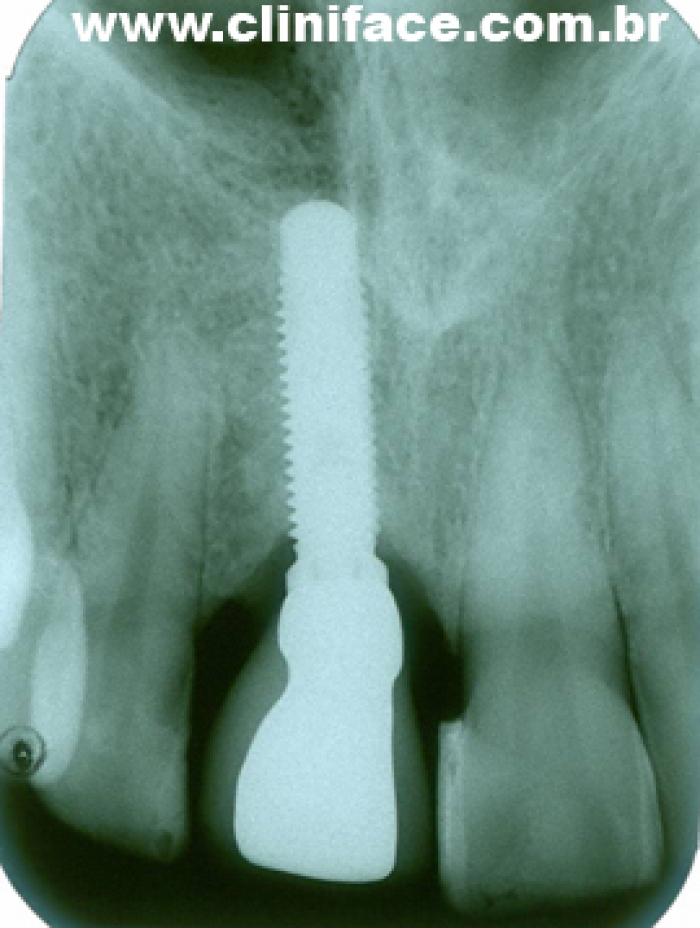

Raio X com prótese de porcelana sobre o implante